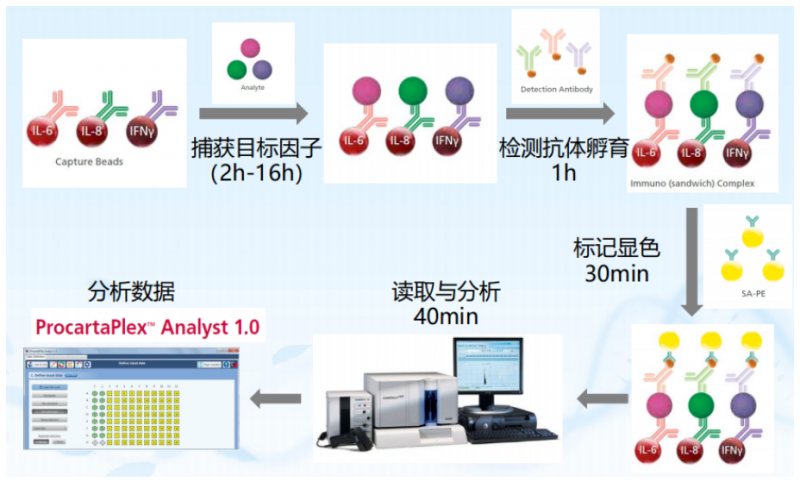

液相悬浮芯片 ,我们前面介绍过 还不知道液相悬浮芯片?你 OUT 啦! 在蛋白检测中的应用,主要是各种细胞因子检测,即 Merck Millipore 公司的 Milliplex 高通量蛋白因子检测芯片。它是一块 96 孔板,每个孔里有偶联上不同抗体的微珠。上样后,经过抗原抗体反应和显色反应,可以得出每个样本的不同因子的量。

细胞因子(cytokines)是由免疫细胞(如单核、巨噬细胞、T 细胞、B 细胞、NK 细胞等)和某些非免疫细胞(内皮细胞、表皮细胞、纤维母细胞等)经刺激而合成、分泌的一类具有广泛生物学活性的小分子蛋白质。也就是说,Miliplex 检测的是各种液体,包括体液、灌洗液。